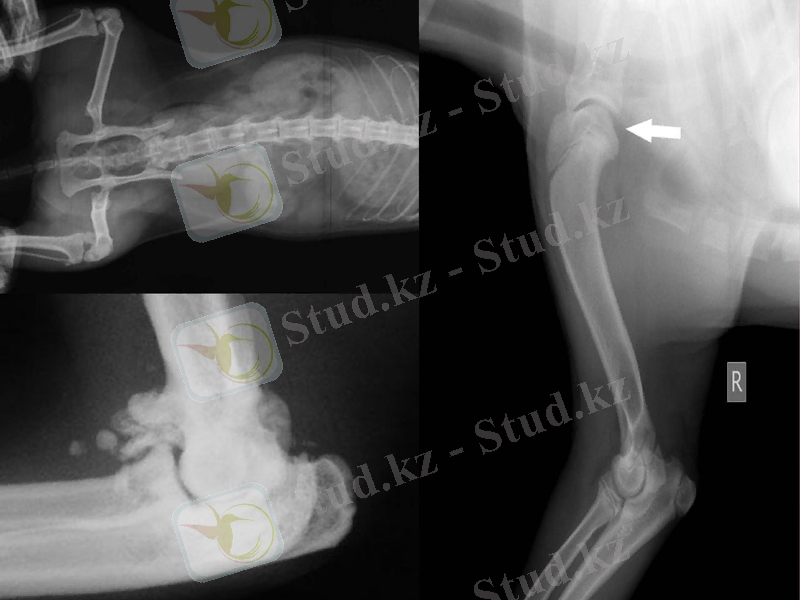

Сүйек ұштарының қалыпты қатынасының бұзылу себептері:

Сүйектердің буын жақ беттерінің бірімен бірінің толық сәйкессіздікте болуы.

Буынның шығуы

Сүйектердің буын жақ беттерінің бірімен бірінің жартылай сәйкессіздікте болуы

Буынның тайып кетуі

Буынның жартылай не толық шыққанын, шыққан буындағы сүйектің маңайындағы сүйек бөлшектерін, сүйекті қоршап жатқан ұлпаның жағдайын көру үшін жамбас немесе иық буындарын рентгенографиялық тәсілмен зерттегенде рентгенпленканың аумағы үлкен болуы керек. Мұндай көлемді суреттер буынның зақымдануынан басқа да жарақаттарды анықтауға мүмкіндік береді.